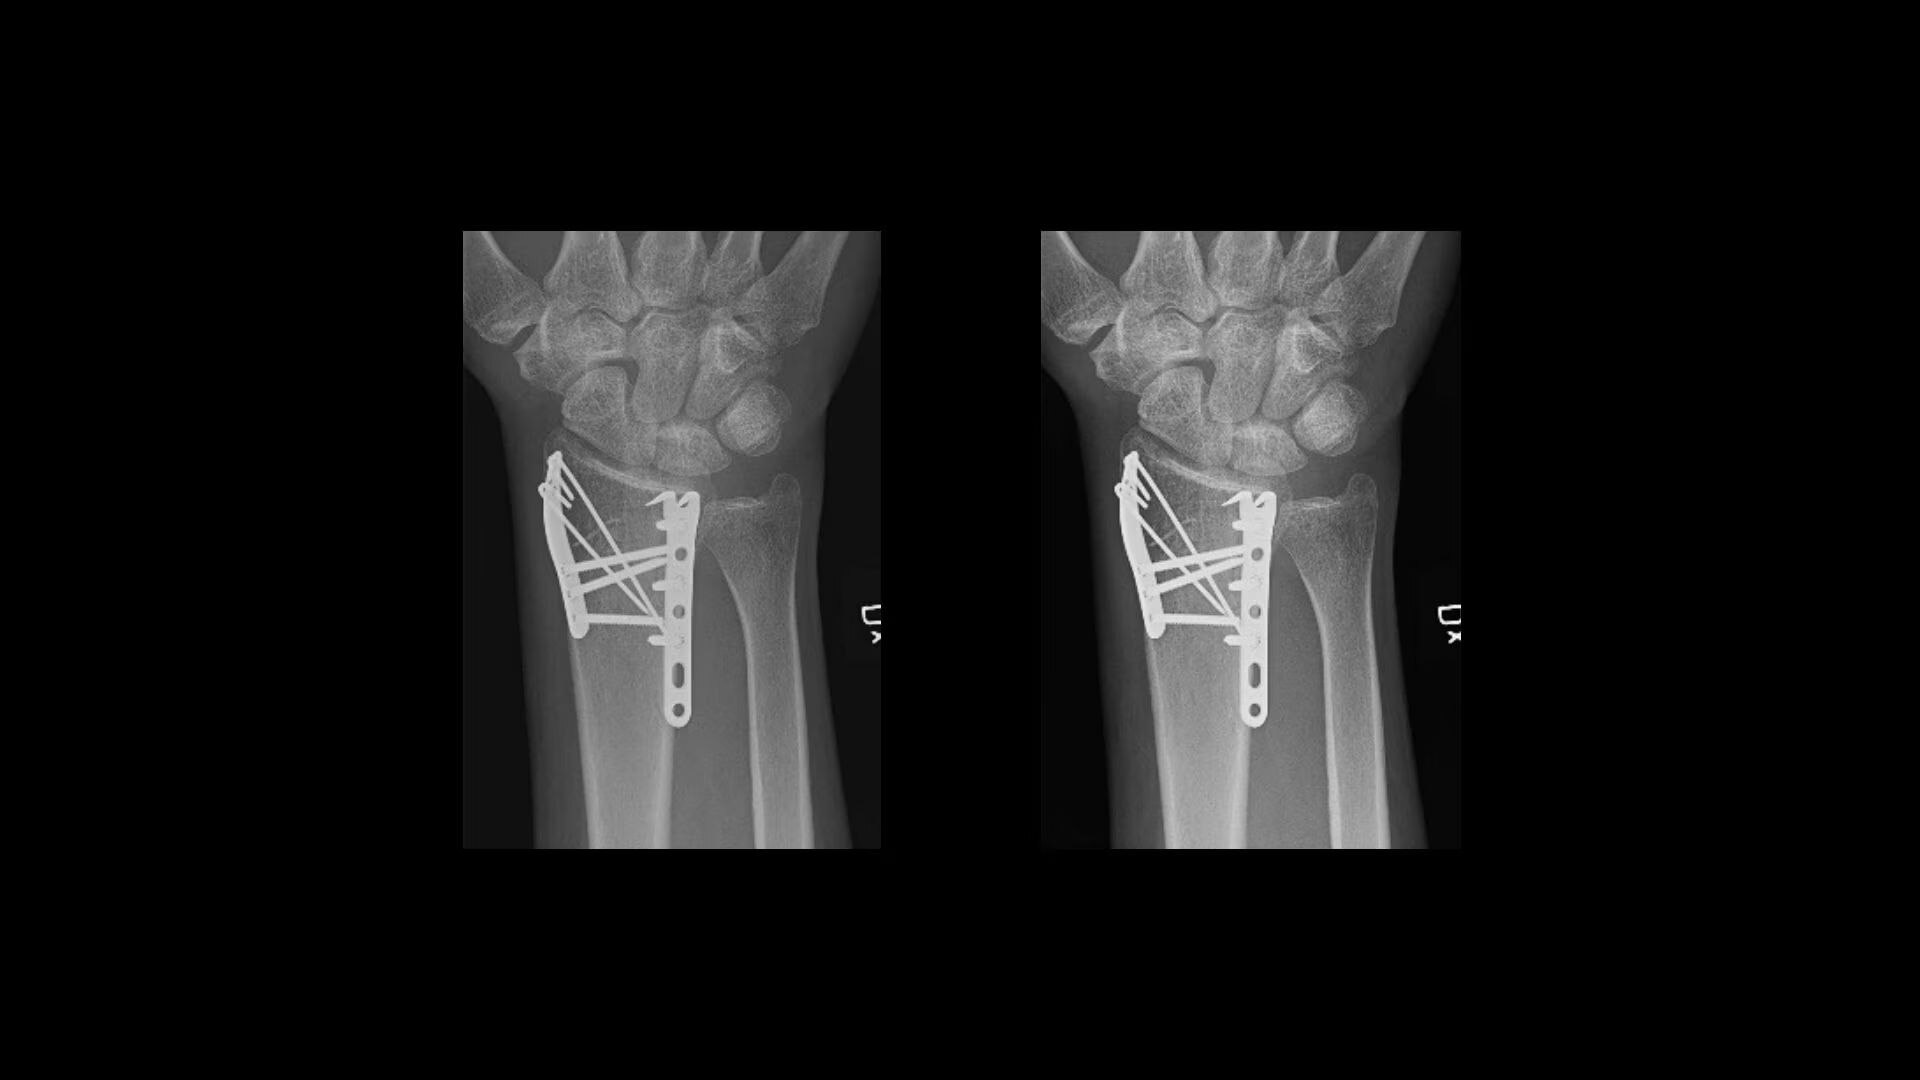

Metal implant handling

See clear bone-metal interface without halo artifact

Helix™ Advanced Image Processing offers unparalleled sharpness, balanced contrast, and optimal brightness, even in the face of dose and patient anatomy variations, as well as challenging metal implants. Available on all of our fixed and mobile X-ray systems, Helix provides consistent performance regardless of exposure technique or exam conditions.